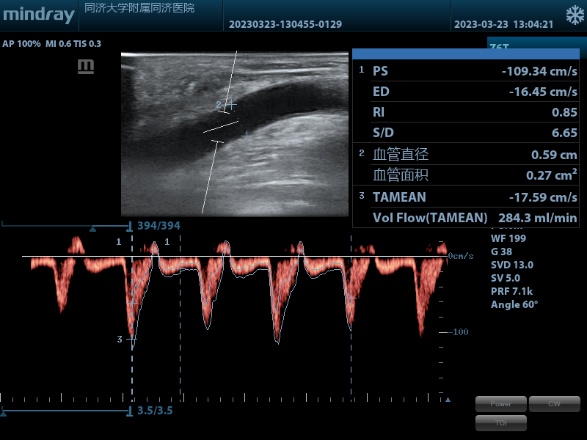

术后血流量

经充分的术前评估准备后,由主治医师张昆负责完成了该台超声下球囊扩张术,术中使用高压药物涂层球囊成功治疗了自体动静脉内瘘的狭窄病变,术后武先生即按原安排进行血液透析,透析顺利,截止目前随访良好。

经过科室内讨论后,根据目前共识及临床试验证据,对于这种静脉血管内膜增生病变建议可以使用药涂球囊干预延长通畅时间,本次结合近心端正常静脉内径,选择了合适型号的新型高压药涂球囊进行扩张治疗。